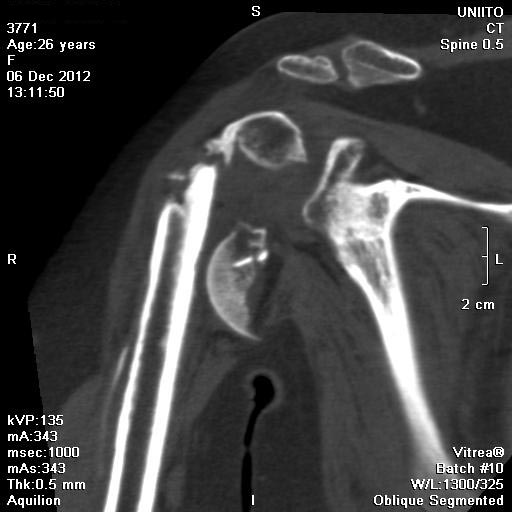

Преимущественное поражение аксиллярного и лучевого нервов...

Имя     : mpr010.jpg